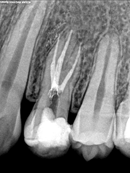

Root Canal Cases